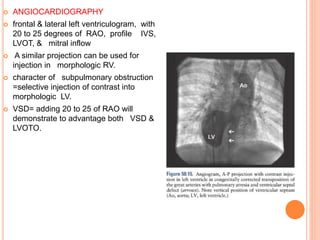

 ANGIOCARDIOGRAPHY

 frontal & lateral left ventriculogram, with

20 to 25 degrees of RAO, profile IVS,

LVOT, & mitral inflow

 A similar projection can be used for

injection in morphologic RV.

 character of subpulmonary obstruction

=selective injection of contrast into

morphologic LV.

 VSD= adding 20 to 25 of RAO will

demonstrate to advantage both VSD &

LVOTO.